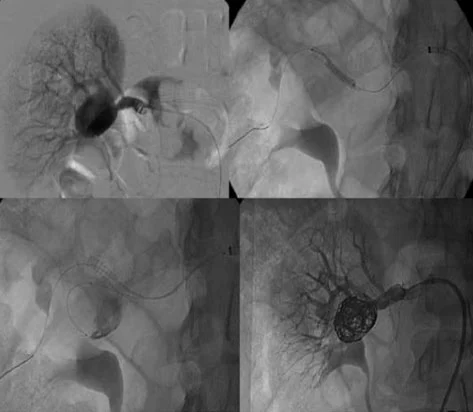

Uno pseudo aneurisma è una dilatazione dell’arteria che coinvolge solo uno strato del vaso, tipicamente a seguito di un trauma che danneggia l’arteria. In questo caso, il sangue fuoriesce dal vaso e viene contenuto solo parzialmente.

Le arterie splenica e epatica sono le più comunemente interessate da aneurismi viscerali. In particolare, l’arteria splenica è coinvolta nel 60-70% dei casi, mentre l’arteria epatica rappresenta circa il 20% degli aneurismi viscerali.